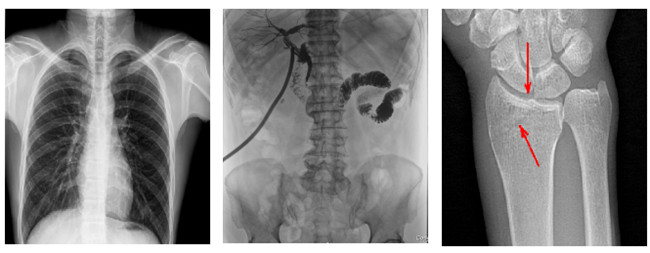

普利德多功能懸吊動態(tài)DR,搭載100μm高品質(zhì)動態(tài)平板探測器,不僅滿足常規(guī)的數(shù)字化X線全身攝影需求,同時還擁有數(shù)字攝影、數(shù)字透視、數(shù)字造影、全景拼接等多種功能,極大地拓展了X線檢查在臨床應(yīng)用范圍,為醫(yī)院臨床應(yīng)用帶來更多實用價值。基于百微平板的高清成像,圖像清晰度與分辨率更高,可滿足不同檢查部位對細節(jié)成像的高品質(zhì)要求,在胸腹部、脊柱等復(fù)雜骨骼和軟組織的攝片上應(yīng)用,更便于觀察隱匿性病灶,精準識別疑難病癥。

不同于靜態(tài)DR拍攝隱匿性病灶時,由于組織重疊病灶難辨,耗費時間更長且易漏診、誤診,普利德多功能懸吊動態(tài)DR可通過動態(tài)實時連續(xù)成像,對于重疊部位病灶或者易被遮擋的病灶進行多角度動態(tài)觀察,毫秒級時間內(nèi)實現(xiàn)動靜態(tài)轉(zhuǎn)換點片,快速、精準完成攝片。比如隱匿性肋骨骨折,可在透視下觀察患者的呼、吸過程,避開重疊影像,快速點片,保證檢查部位的病癥不被遺漏,實現(xiàn)精準診斷。